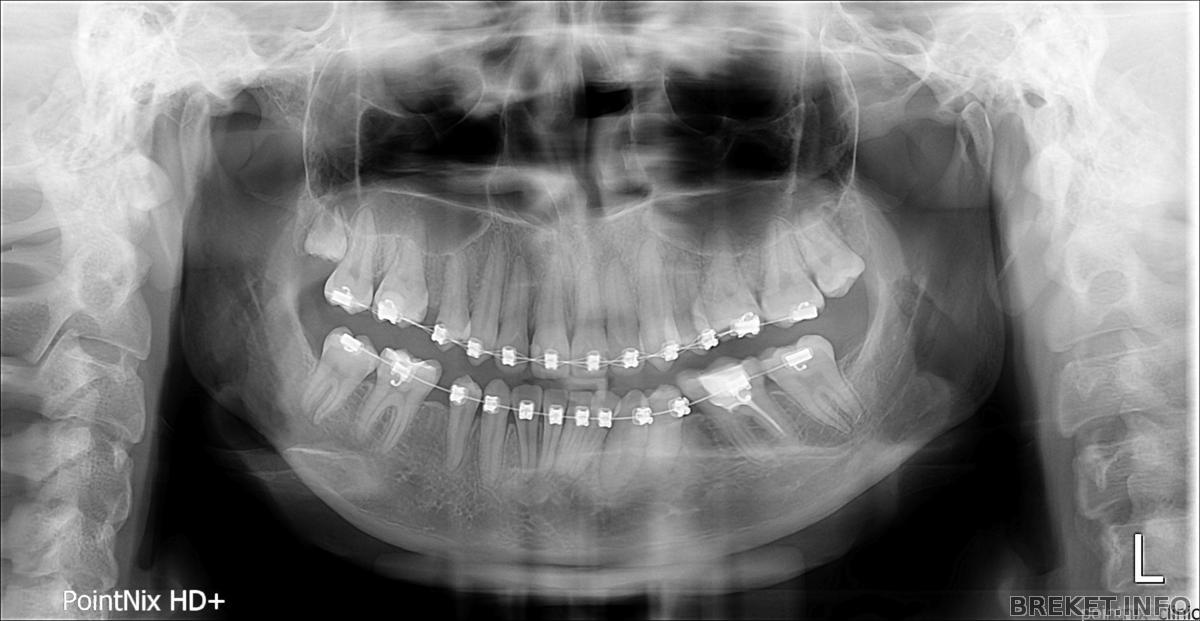

в итоге сделала снимок и я просто в шоке.

на снимке нижний шестой зуб справа.

lebedeva.e.b_p01_20150312_102520516.jpg

один канал просто не увидели. но подозреваю, что просто стало пох, т.к. лечила в бесплатной поликлинике. Читать далее »